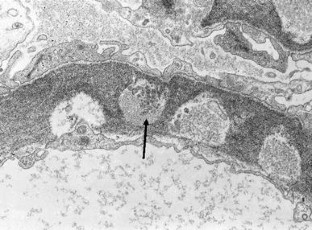

We report an unusual pathological finding, a large-sized bubbling appearance of the glomerular basement membrane (GBM), in a patient with pulmonary limited AL amyloidosis and a past history of lupus nephritis. The first renal biopsy specimen from 10 years ago, when systemic lupus erythematosus was diagnosed, demonstrated mild mesangial proliferation and subepithelial deposits (WHO classification: III + V). Light microscopy of the current biopsy using periodic acid methenamine silver (PAMS) stain demonstrated a large-sized bubbling appearance of the GBM; however, very weak immunoglobulin and complement deposition was observed in immunofluorescence studies. Routine electron microscopy demonstrated partial subendothelial expansion with electron-lucent materials, but no electron-dense deposits or amyloid fibrils. Electron microscopy with PAMS stain revealed electron-lucent endothelial scalloping, including some cellular components and microspheres in the GBM; however, it is not clear if these materials are derived from endothelial cells. One possibility is that these unique findings represent a recovery phase of lupus membranous nephritis; another is that these findings correspond to a new disease entity.

Fig. 2